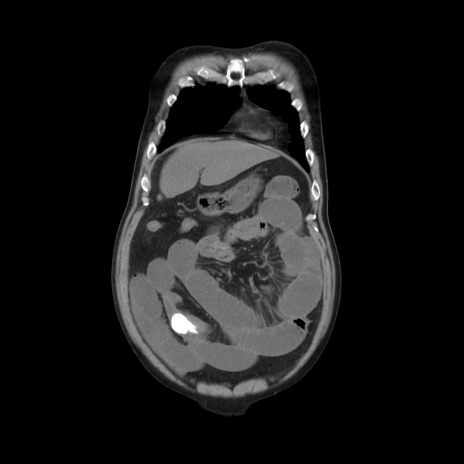

症例20(冠状断像)

【症例】 60歳代男性

【主訴】 腹部膨満、嘔吐

【現病歴】5日前頃より倦怠感を認め食事量減少し4日前の朝嘔吐、食事摂取困難となった。 3日前近医受診し点滴施行され整腸剤などを処方された。 当日他院を受診し、腹部膨満著明、炎症反応の上昇(CRP10.8、WBC11200)あり、紹介受診となる。

【身体所見】 意識JCS1 受け答えがはっきりしないBP 111/57mHg、 P 67bpm、、BT35.2°C、SpO2 97%(RA)、 腹部:膨隆、打診で鼓音あり、全体的に圧痛有り、腸蠕動音(-)、反跳痛ははっきりせず。

【データ】WBC 11400、CRP 14.20